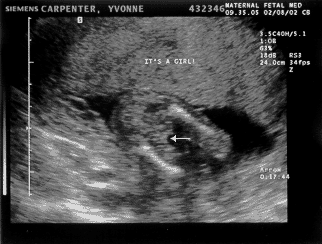

The MY baby’s 2nd test — February 8th — 17 weeks

I am getting big! Matt: Amniocentesis day! This is the big daddy of tests. Although I was there I can’t comment on how it went since the needle was not in me. At one point I got up to hold Yvonne’s hand but the doctor kindly asked me to sit down. Seems that some dads pass out and they don’t want any cracked skulls on their hands. Before the big poke however the MY baby went trough a battery of measurements via ultrasound. My, how we have grown! As this scan shows we are looking downright human in there. Also I won’t have to call the MY baby two names every time I talk to it because we found out the answer to that little question. However since Yvonne was the one getting stuck I will let her have the pleasure of sharing the news. At any rate, all measurements came back normal and we will get the results of the amnio in 8-10 days.

It's a girl! Yvonne: Phew! I am glad we are over the amnio hump. It was not exactly painless, but it wasn’t nearly as painful as I imagined it. I got 3 pokes, 2 from the anesthetic and 1 from the real needle. The whole thing was done in about 3 or 4 minutes and after I got a “beep-beep” band-aid on my “owy” we were presented with 2 little tubes of yellowish liquid. I confirmed that the name on the tubes was mine and off they went to the lab. The exciting part though was the ultrasound done before the test. They turned the baby upside down (so to speak) measuring every little piece of its body and looking for anything suspicious. There seems to be quite a few things that can go wrong and still take a baby this far into the pregnancy, but thankfully nothing was found — and it wasn’t for lack of searching!! For example, they spent almost 5 minutes on the spine alone, checking every set of 2 or 3 vertebras to make sure they looked right and did not have a gap. Kyla passed this part of the test and gave us a thumbs up on one of the ultrasound views:-) You read it right, no more Luke/Kyla — for now on (95% sure anyway) it is Kyla only!! Luke will have to wait for his turn!